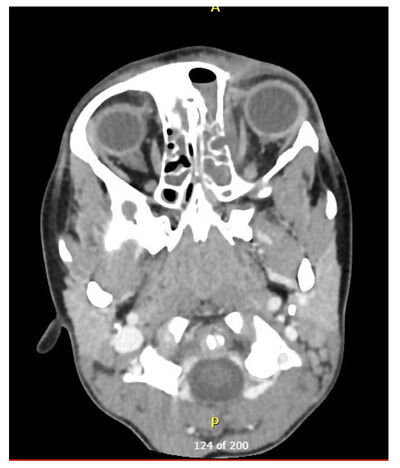

Hálfum sólarhring síðar kom drengurinn aftur á bráðamóttöku, þá með hratt vaxandi einkenni. Mikill og skarplega afmarkaður roði hafði komið fram í kringum bólgna svæðið og einnig hafði drengurinn nýtilkomna verki við allar augnhreyfingar ásamt ljósfælni. Hann hafði vægan roða í koki en kverkeitlar voru eðlilegir og engar eitlastækkanir á hálsi. Drengurinn var með 38°C hita sem svaraði illa hitalækkandi meðferð en lífsmörk voru annars innan eðlilegra marka. Blóðrannsóknir sýndu CRP 89 mg/L og 14,4 x10E9/L hvít blóðkorn. Tölvusneiðmynd af auga sýndi skútabólgu og beinhimnuígerð miðlægt í vinstri augntótt, 20 x 4 mm að stærð (mynd 5), og var hafin meðferð með ceftriaxone og clindamycin í æð.

Mynd 5. Tölvusneiðmynd tekin á innlagnardegi sem sýnir ígerð miðlægt í vinstri augntótt og alskyggða skúta.